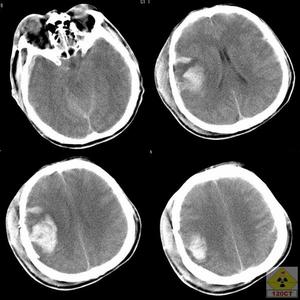

3.顱腦CT掃描CT掃描對顱骨碎片、彈片、創道、顱內積氣、顱內血腫、瀰漫性腦水腫和腦室擴大等情況的診斷,既正確又迅速,對內科療效的監護也有特殊價值。

(1)火器傷顱內血腫

③在傷情許可下,應攝頭顱X線平片,行CT掃描。

④出現腦疝時,應迅速將射入口骨窗擴大,清除血腫並止血;如果患者已在專科醫療單位,則清除血腫和腦清創術應一期完成。⑤遠處或對側半球皮質表面金屬異物所引起的血腫,應另作骨瓣開顱清除。然後作入口處清創。